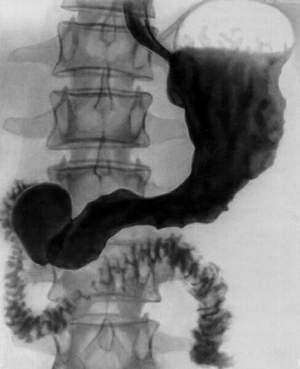

Почему нужно выполнять второй способ обследования? Все дело в том, что желудок является полым органом. А потому у него способности задерживать рентгеновские лучи. Чтобы результат был верным, контраст принимается в два этапа: Первый прием предполагает употребление небольшого глотка. В этот момент врач дает оценку глотательному процессу, прохождению жидкости по пищеводу. После этого раствор полностью обволакивает желудочные стенки. Потом врач производит несколько снимков и запечатлевает рельеф складок на органе.

Второй этап подразумевает прием остатков раствора. Это примерно 100-150 миллилитров. В этот момент благодаря прохождению бария по органу доктор может разглядеть форму, расположение и размер желудка. Также оценивается тонус и перистальтика.

Снимки делают в нескольких проекциях, поэтому больному приходится менять положение. Одним из таких является поза Тренделенбурга. Медицинский стол наклоняется так, чтобы таз пациента находился выше головы. Это помогает выявить грыжу в пищеводном отверстии.

Результат обследования зависит и от того, какая проекция органа рассматривается. На прямых снимках можно разглядеть рельеф антральной области желудка и пищевода после употребления первых глотков жидкости, состояние складок и бороздок в верхнем отделе органа, функциональность перехода между желудком и кишечником.

Также рассматриваются косые и боковые проекции. Благодаря им можно увидеть пневморельеф антральной области, функциональность привратника, смещенность, желудочно-пищеводного рефлюкса.